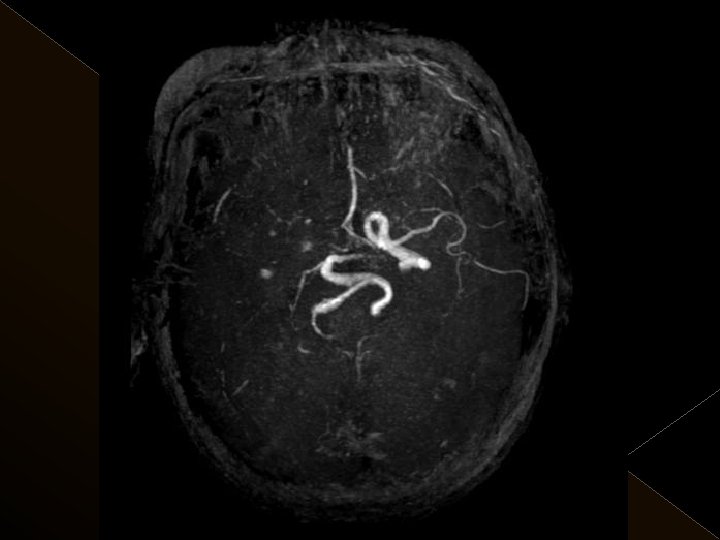

Görüntüleme İşlem öncesi § Bazal kontrastsız BT § BT anjiografi (varsa perfüzyon BT ) § MR (DW, ADC) İşlem sonrası § MR ( DW, ADC, SWI) § 24. saatte kontrol BT veya MR